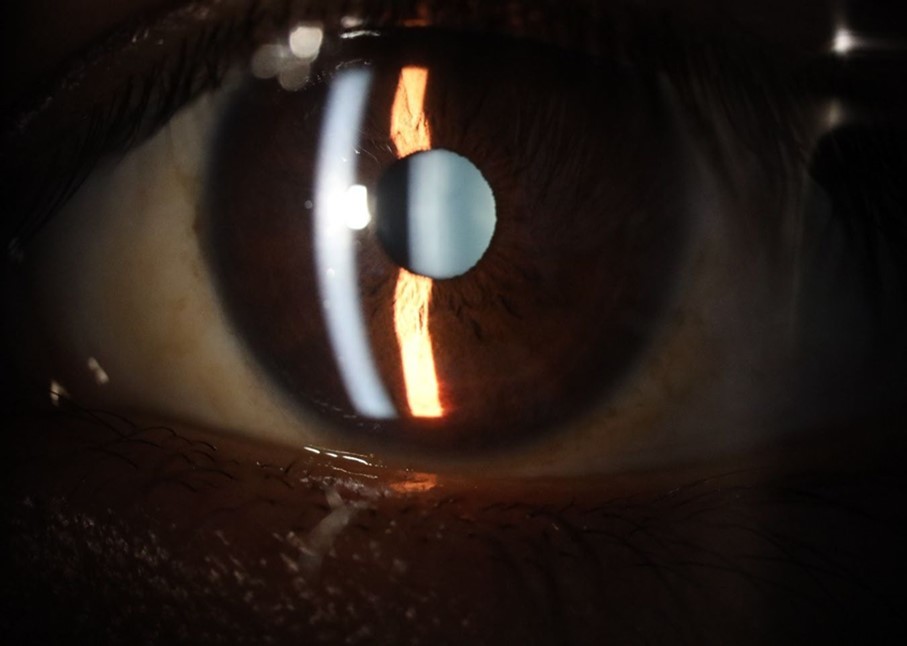

Figure 5.The slit-lamp photograph shows the anterior segment, relatively unscathed, in terms of transparent media (Cornea, crystalline and vitreous).

The slit-lamp photograph shows the anterior segment, relatively unscathed, in terms of transparent media (Cornea, crystalline and vitreous).

Figure 6.Slit-lamp examination showed a solution of continuity in the left temporal region, which fortunately only affected the conjunctiva and Tenon's capsule, while the sclera was unscathed.

Slit-lamp examination showed a solution of continuity in the left temporal  region, which fortunately only affected the conjunctiva and Tenon's capsule, while the sclera was unscathed.